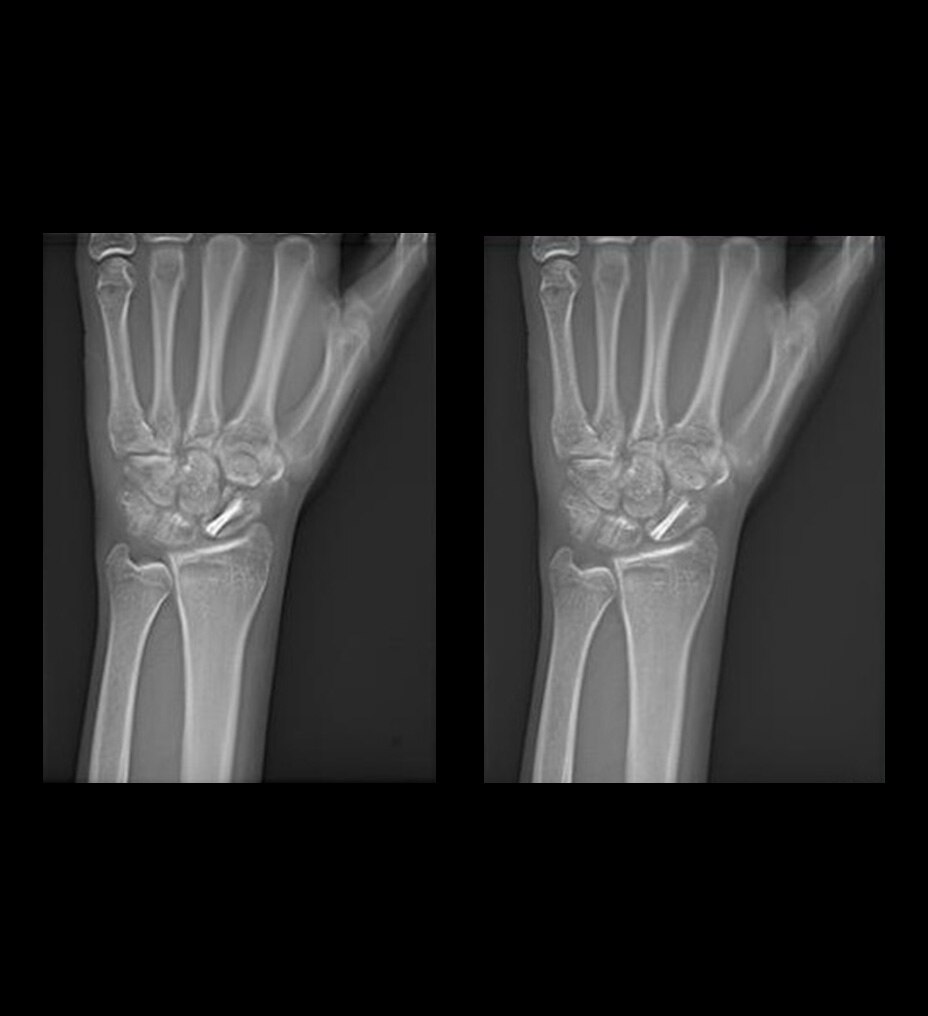

Le gadobutrol est formulé avec une concentration deux fois plus élevée en ions Gd³⁺ que les autres agents de contraste à base de gadolinium (GBCA), ce qui permet de réduire de moitié le volume d’injection tout en produisant un bolus plus ciblé. Combiné à une relaxivité r1 élevée, le gadobutrol améliore la détection, la délimitation et la caractérisation en IRM2,3,8-11.

Très efficace en imagerie à l’état stable comme en imagerie dynamique 2-6,12

Potentiel d'amélioration de la confiance diagnostique dans un large éventail d'indications11,13,14